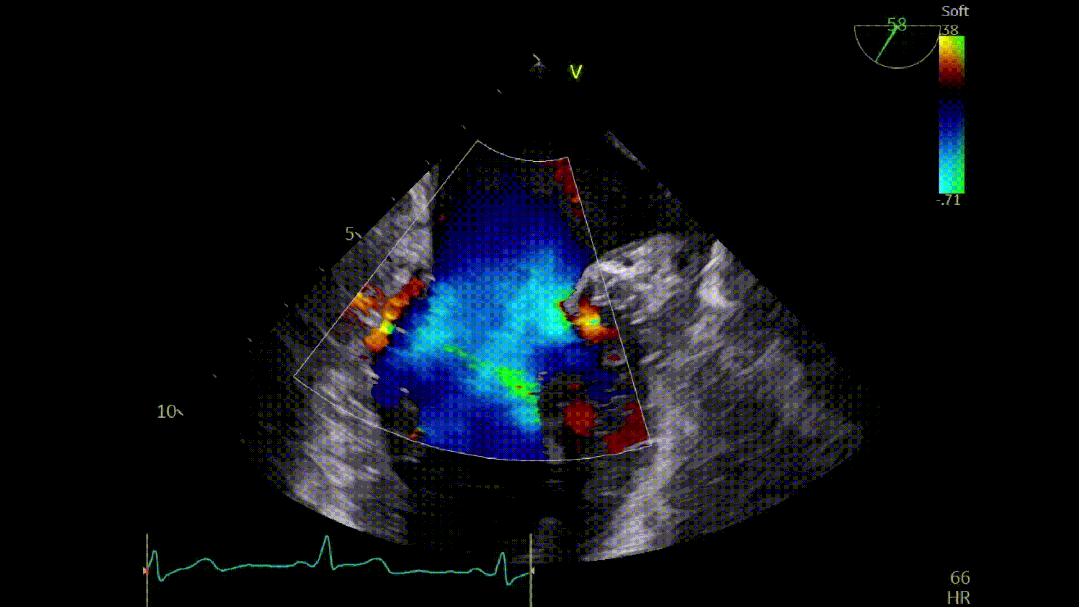

本次培训的“重头戏”—— 两台高难度 TEER 手术沉浸式观摩,将培训氛围推向高潮。手术病例分别为 “P2 宽大脱垂病变” 与 “早期 Barlow 病变”,由厦门大学心血管病医院团队与浙江大学附属邵逸夫医院团队协同完成。术中,专家团队操作精准、配合默契,不仅完美展现了 TEER 技术在复杂病例中的应用优势,更通过实时讲解,让学员直观掌握手术关键步骤、解剖评估要点与应急处理思路。

病例1: